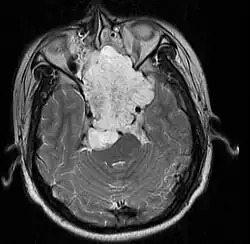

| MRI of extensive clival chordoma in 17-year-old male patient, axial view. Tumor in the nasopharynx extending from nasal cavity to brainstem posteriorly is clearly visible. | |

Chordomas can arise from bone in the skull base and anywhere along the spine. The two most common locations are cranially at the clivus and in the sacrum at the bottom of the spine.[2] Very rarely, chordomas present outside of the skull base or spine; these are called extra axial chordomas.[3]